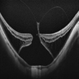

- vitreoschitic membrane

- vitreoschisis, myopic traction maculopathy

- intra operative photograph, SONY camera

- Triamcinolone enhanced visualization of vitreoschisis membrane and removal in a case of myopic traction maculopathy.